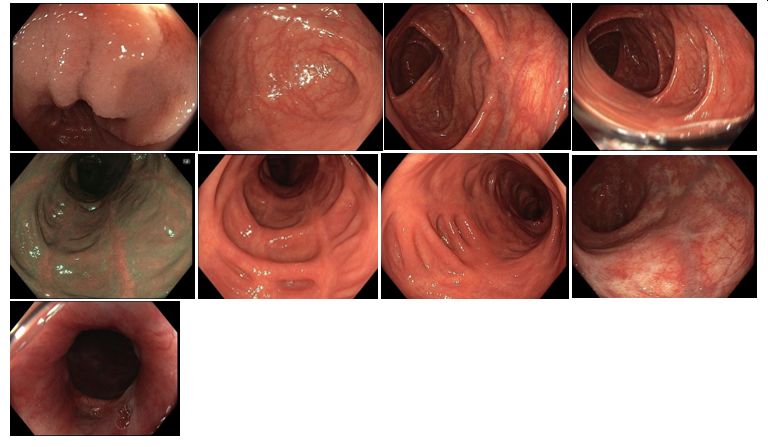

Koloskopie 2014: Endoskopický obraz mírné segmentální pankolitidy (aftózní léze, nálety fibrinu, reziduální drobné ulcerace po původně serpiginózních vředech). Nápadné pozánětlivé změny (jizvy, polypy), retrakce zejména v levém tračníku. Normální terminální ileum

Koloskopie 2017/2: Aktivní zánětlivé změny (serpiginózní ulcerace) v oblasti rektosigmatu, mírné zánětlivé změny v blízkosti hepatálního ohbí, segmentálně pozánětlivé změny zejména v levém tračníku (jizvy, retrakce). Normální terminální ileum

Koloskopie 2018/8: Mírné floridní zánětlivé změny (ložiskové zarudnutí a setřelá podslizniční cévní kresba, aftoidní léze) v blízkosti hepatálního ohbí v colon ascendens a v sigmatu. Pozánětlivé změny (jizvy po serpiginózních ulcerací v příčném a levém tračníku, vlevo i pozánětlivá trabekulizace. Normální terminální ileum.

Koloskopie 2022/2: Pozánětlivé změny celého tračníku (jizvy), v rektosigmatu je reziduální ulcerace v centru serpiginózní ulcerace – bez makroskopických známek aktivity v tračníku i terminálním ileu. Vyšetření v bílém světle i NBI